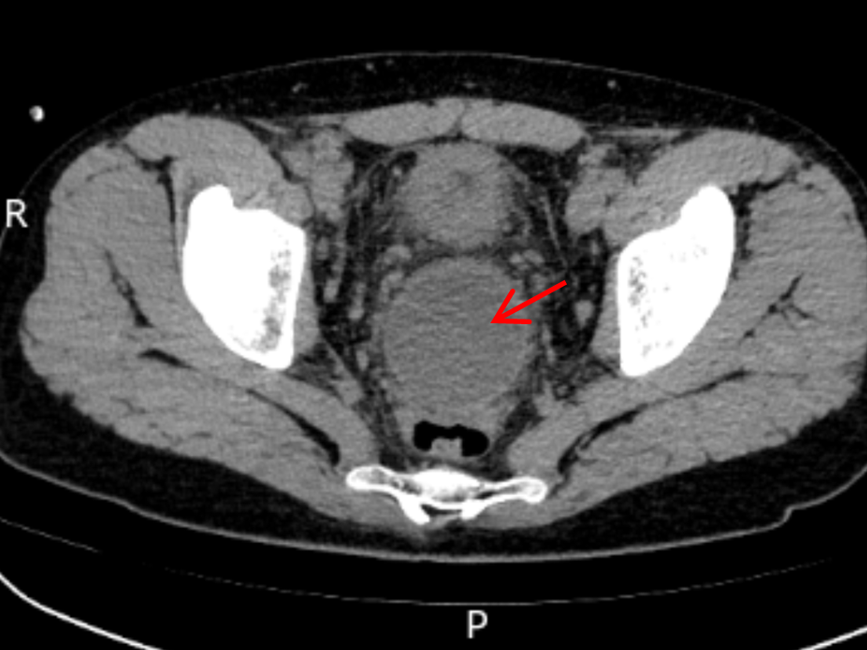

术前CT显示直肠前方一直径5cm圆形脓肿

术后4天复查CT显示脓肿基本消失

术后4小时,大量脓液即经肛门顺利排出,患者发热症状消退;术后2天,尿频、尿急、肛门下坠等不适症状完全缓解;术后4天复查CT显示,盆腔脓肿已基本消退;术后5天,患者顺利康复出院。出院前,患者含泪对医护团队表达感谢:“医者仁心,你们不仅治好了我身体的病痛,更治愈了我心底的恐慌,感谢青大附院的医护人员们。”